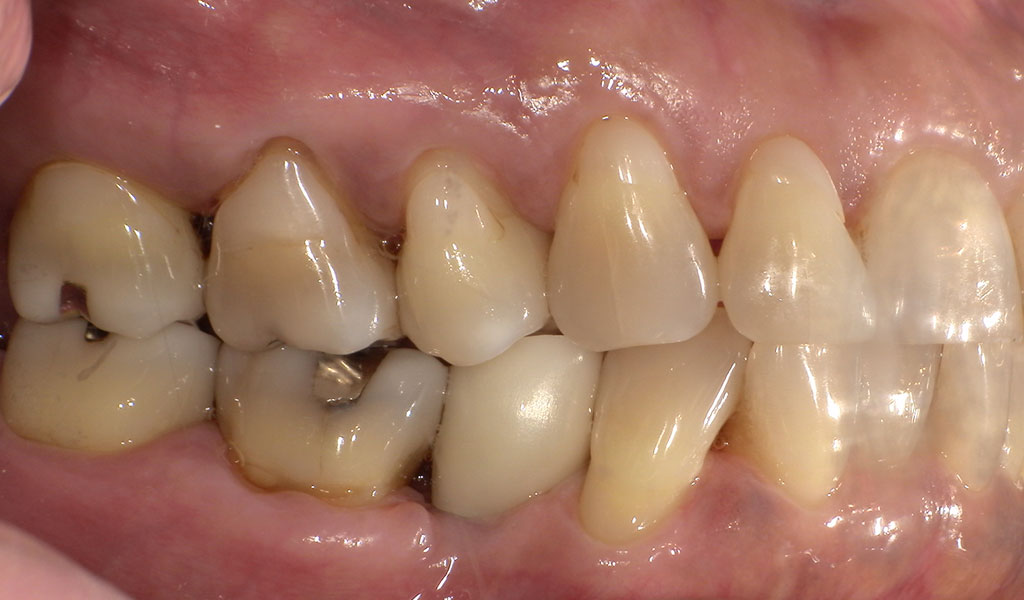

Before1(右下4番)

Before2(左下4番)